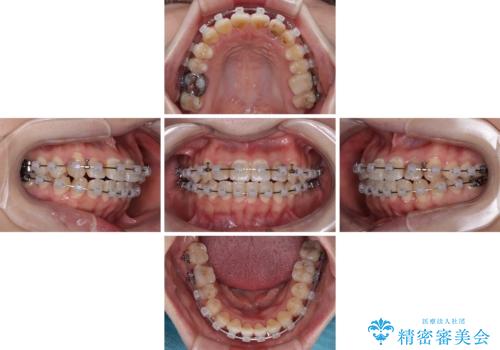

- 矯正装置

- クリアブラケット

- 1年5ヶ月

急速拡大が奏効し、非抜歯矯正にて八重歯を解決することができました。